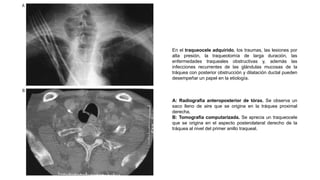

En el traqueocele adquirido, los traumas, las lesiones por

alta presión, la traqueotomía de larga duración, las

enfermedades traqueales obstructivas y, además las

infecciones recurrentes de las glándulas mucosas de la

tráquea con posterior obstrucción y dilatación ductal pueden

desempeñar un papel en la etiología.

A: Radiografía anteroposterior de tórax. Se observa un

saco lleno de aire que se origina en la tráquea proximal

derecha.

B: Tomografía computarizada. Se aprecia un traqueocele

que se origina en el aspecto posterolateral derecho de la

tráquea al nivel del primer anillo traqueal.